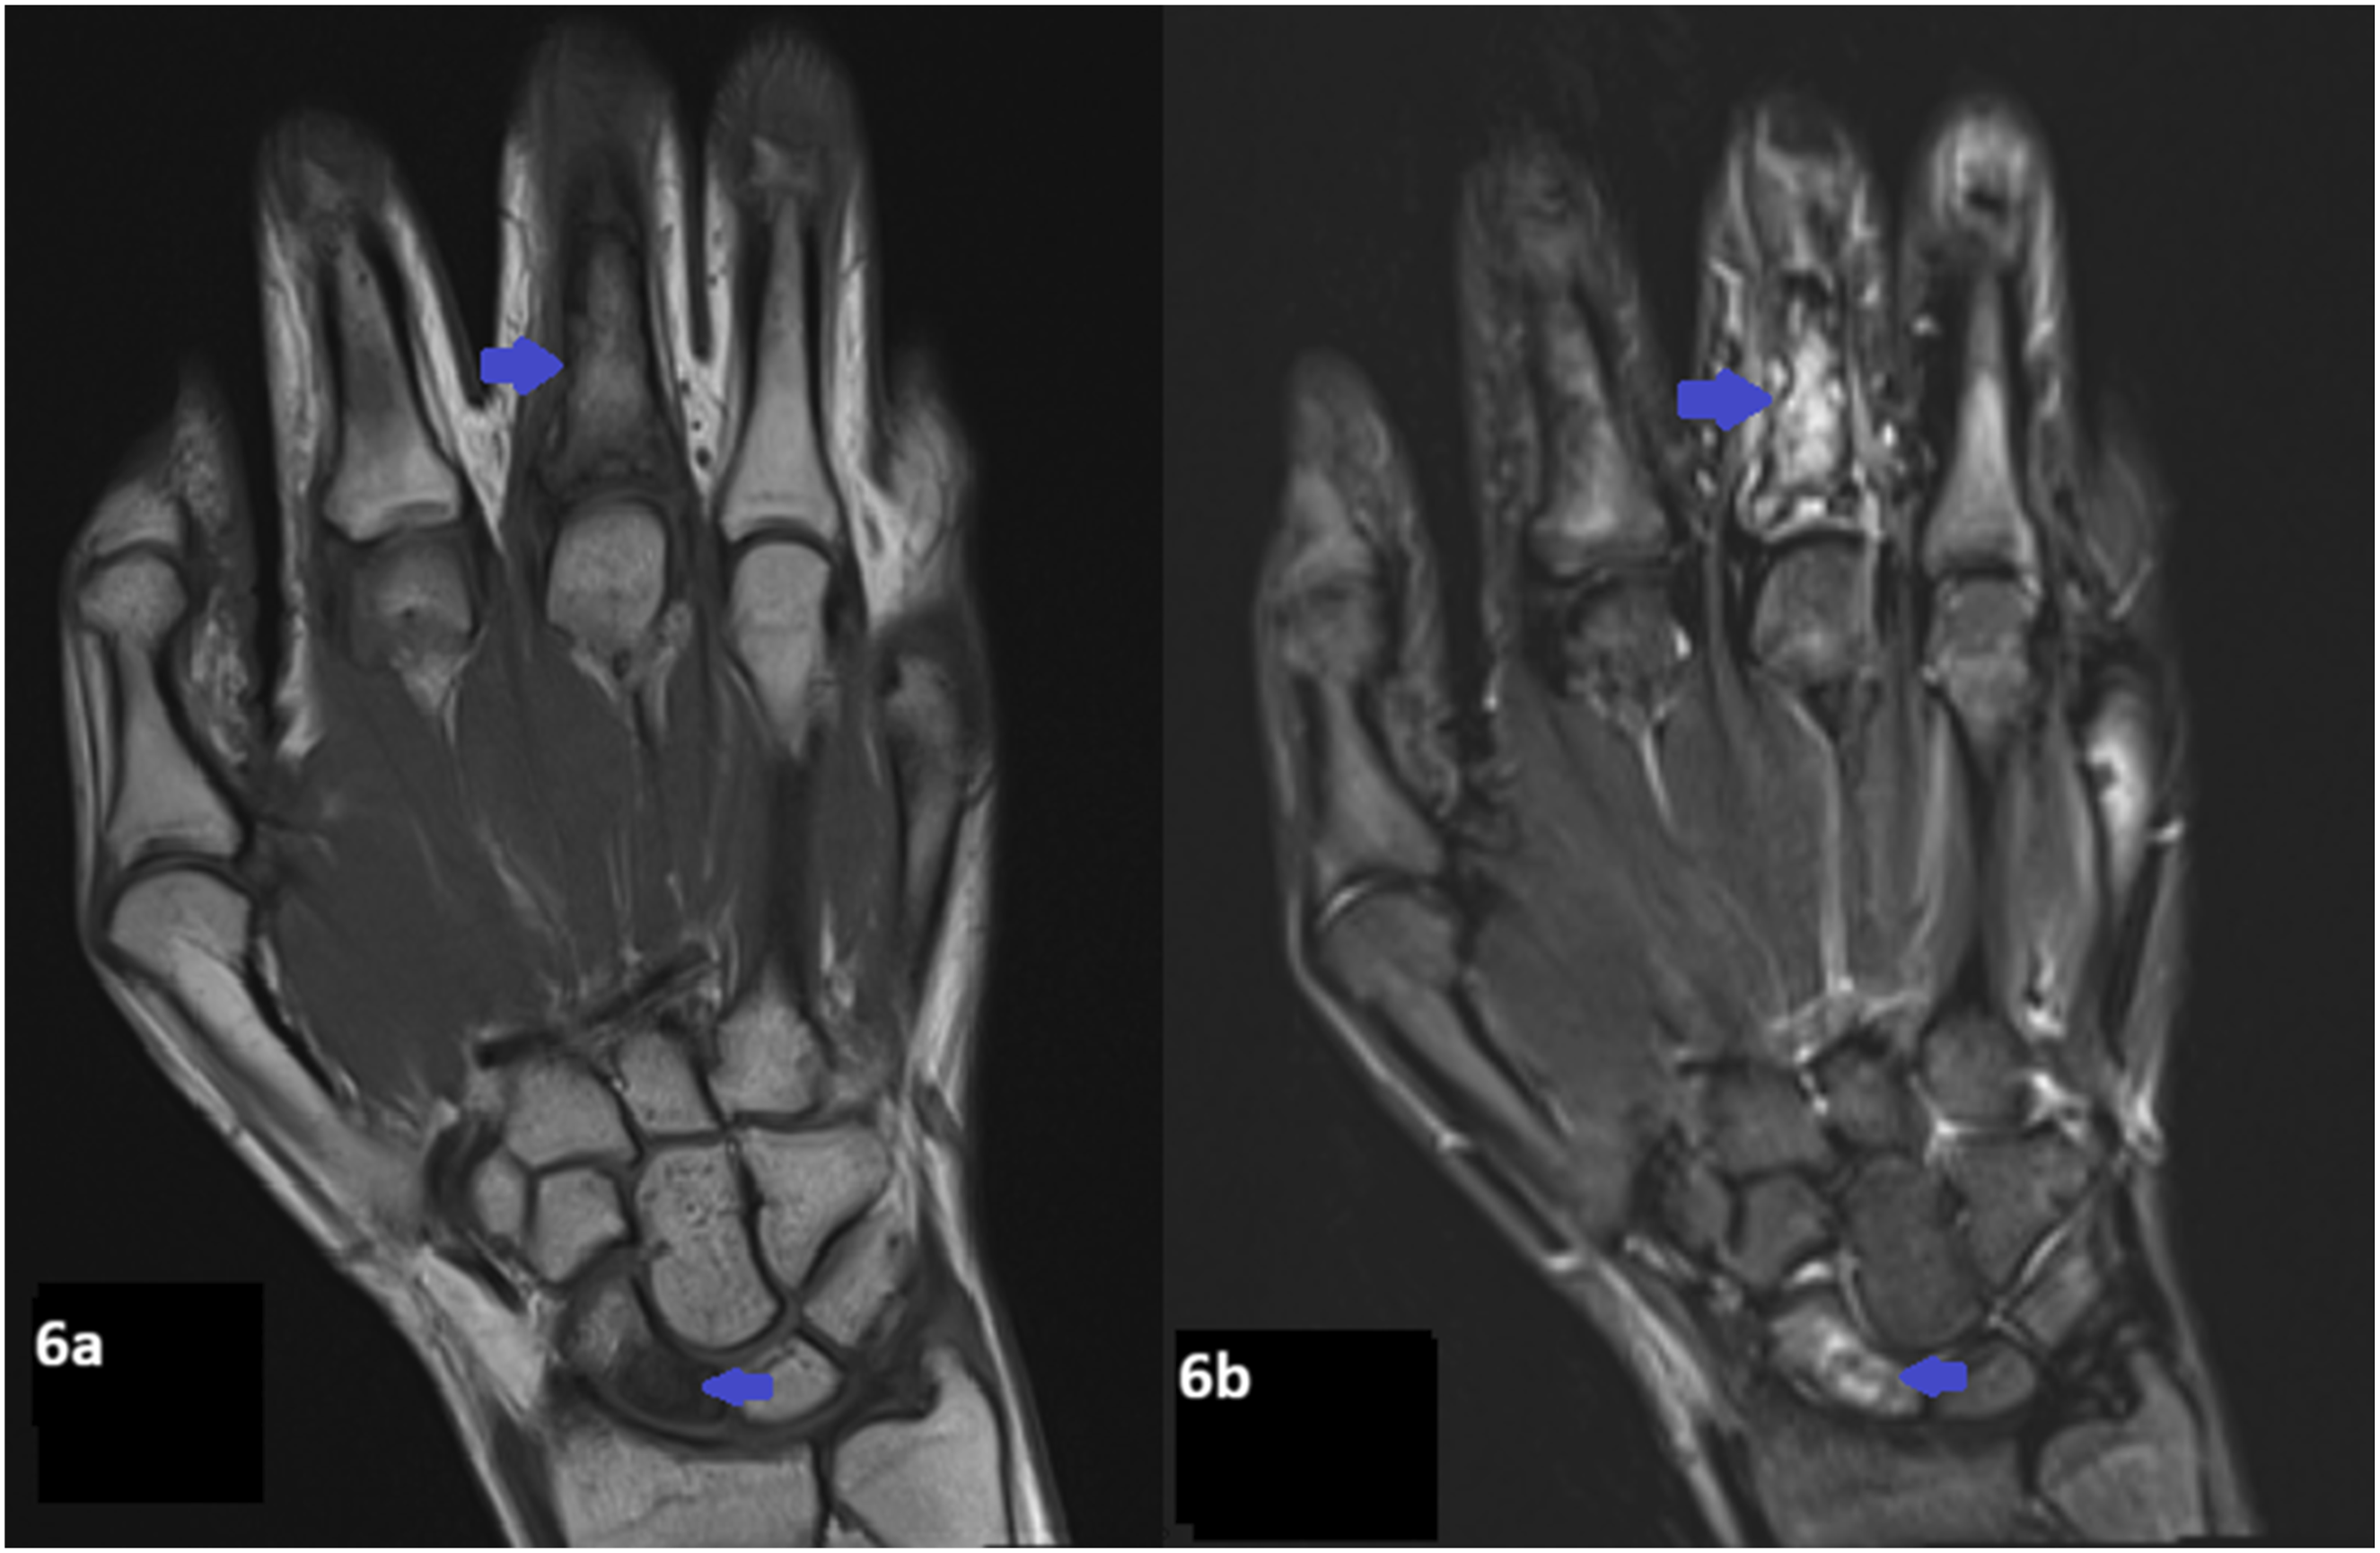

Radiographs of the hands revealed multifocal permeative lucencies involving the distal radius and multiple phalanges (Figure 5), raising concern for systemic arthropathy or osteomyelitis. MRI of the hands showed bone marrow signal abnormalities consistent with multiple bone infarcts (Figures 6–8). Radiographs of the hand showing permeative lytic lesions involving left distal radius and multiple phalanges (blue arrows). (a) Coronal T1W and (b) Coronal STIR MRI of the right hand reveals bone infarcts at the scaphoid and middle finger proximal phalanx. (a) Coronal T1W and (b) STIR MRI of the left hand demonstrates patchy T1 hypointense signal and STIR hyperintense signal abnormality at the distal radius representing ischemic changes. (a) Coronal T1W, (b) Coronal STIR, (c) Axial STIR, and (d) Post contrast T1FS of the left hand demonstrates bone infarct at the ring finger proximal phalanx, and soft tissue edema and enhancement.